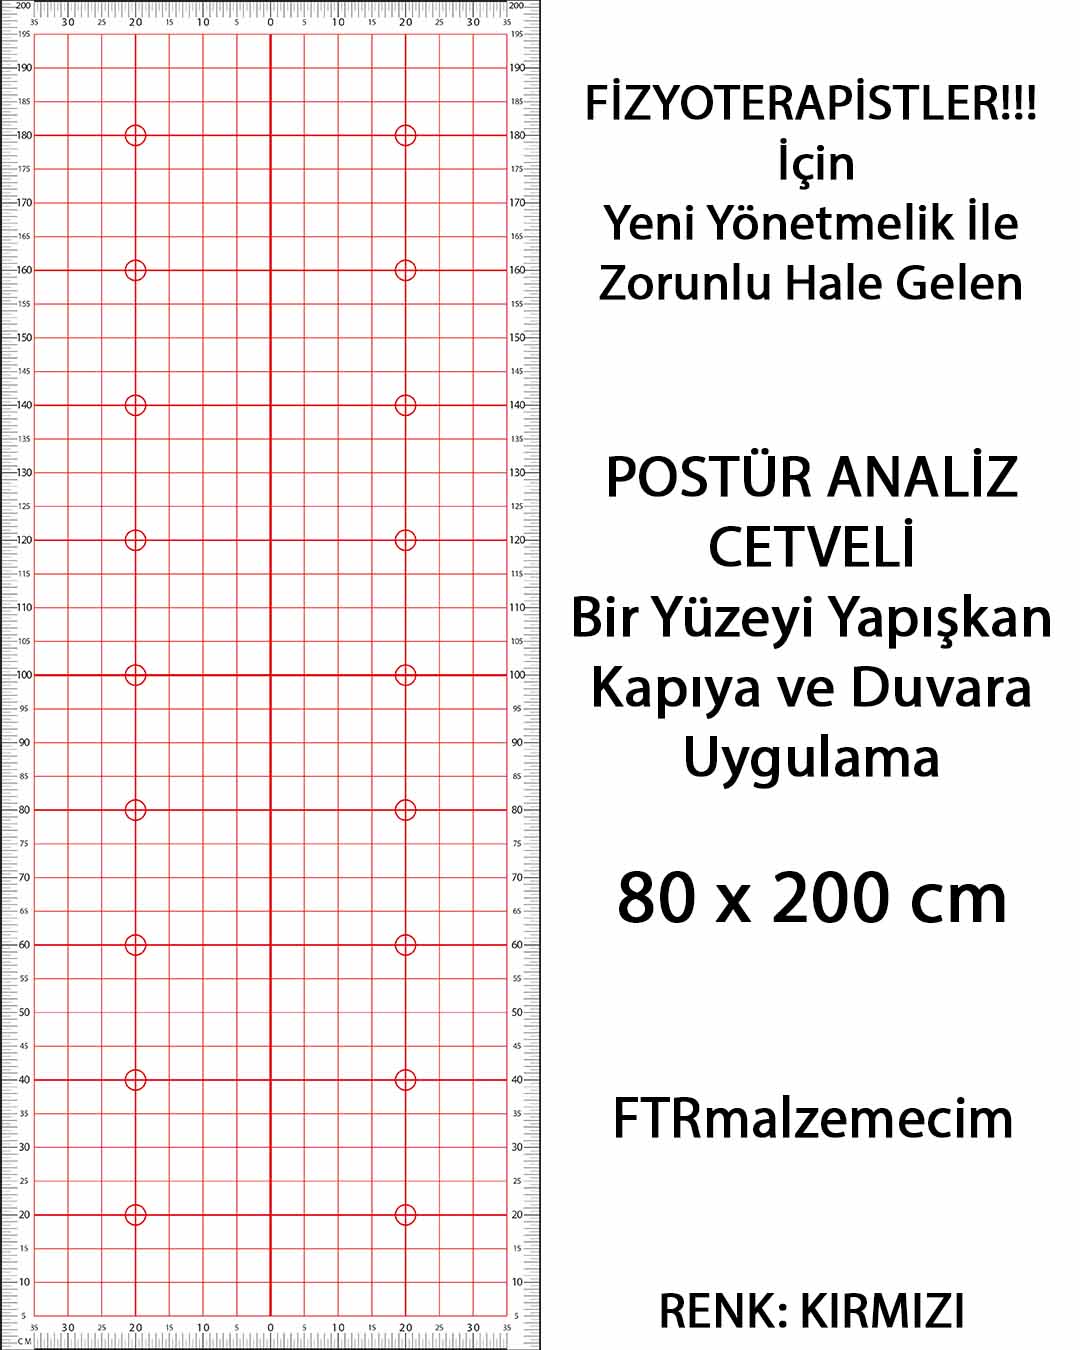

Ftrmalzemecim.com’da; egzersiz ekipmanlarından elektroterapi cihazlarına, sıcak-soğuk uygulama ürünlerinden yürüteç, baston ve tekerlekli sandalye gibi yardımcı ekipmanlara kadar geniş bir ürün yelpazesi bulunmaktadır. Ürünlerimiz, uzman fizyoterapistler tarafından test edilmekte ve klinik kullanıma uygunluğu onaylanarak satışa sunulmaktadır. Her biri Sağlık Bakanlığı onaylı, kaliteli ve güvenilir ürünlerdir.

Yeni bir fizik tedavi merkezi kurmayı planlayan fizyoterapistlere A’dan Z’ye klinik kurulum danışmanlığı sunmaktayız. Gerekli ekipman listesinin oluşturulmasından yönetmeliklere uygun ürün seçimine kadar tüm süreçlerde profesyonel destek sağlıyoruz. Güncel mevzuatı yakından takip eden uzman kadromuzla, sadece ürün değil, bilgi ve çözüm de sunuyoruz.